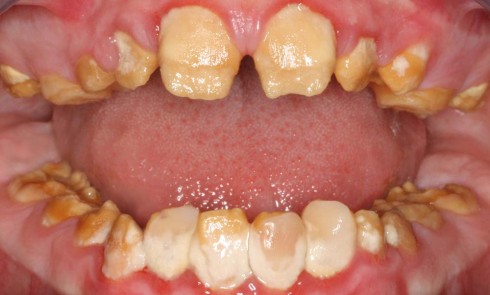

Définition L’amélogenèse imparfaite est le nom donné à un groupe hétérogène de pathologies caractérisées par un défaut inné du développement...

L’amélogenèse imparfaite (AI) est une anomalie héréditaire rare de la structure dentaire, caractérisée par des défauts amélaires en denture temporaire...

Une pathologie est dite rare lorsqu’elle affecte moins d’un individu sur 2 000 dans une population. Les amélogenèses imparfaites héréditaires (AIH)...